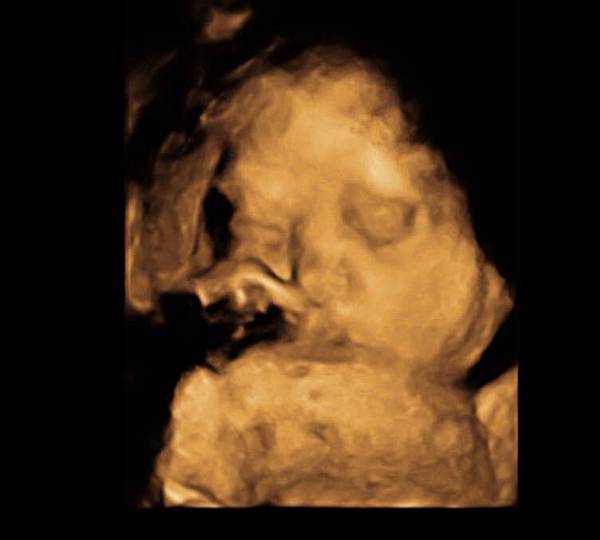

今天禾馨護理師打來約定入院時間

2/1 星期天晚上7點報到

待產包都準備好了

小宇也溝通好這幾天要住外婆家囉~